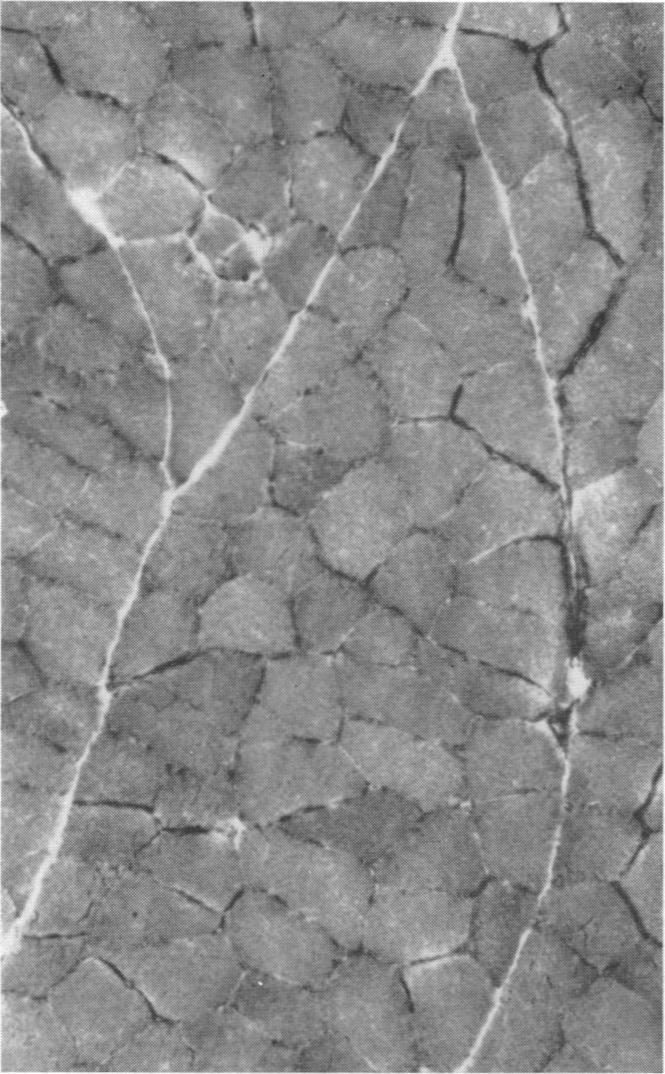

1. Cross-innervation of the slow soleus and fast flexor hallucis longus or flexor digitorum longus muscles has been performed in new-born kittens and rabbits and in adult cats.2. The effects on the histochemical and structural properties of the muscle have been studied and compared with the changes in the contractile properties.3. Cross-innervation has produced a dramatic change in histochemical pattern in the fast muscles, with the development of areas of muscle fibres indistinguishable from normal soleus muscle. The converse change from the histochemical pattern of slow soleus to that of fast muscle has also occurred, but has been less consistent.4. It is concluded that the neural influence determining the contractile properties of fast and slow muscle also has a profound controlling influence on the structure and metabolic activity of the muscle fibres.5. No significant changes could be demonstrated biochemically in the ATPase activities of the fast and slow muscles following cross-innervation.

3. 交叉神经支配使快肌的组织化学模式发生了显著变化,出现了与正常比目鱼肌难以区分的肌纤维区域。从慢比目鱼肌的组织化学模式向快肌模式的相反变化也有发生,但不太一致。